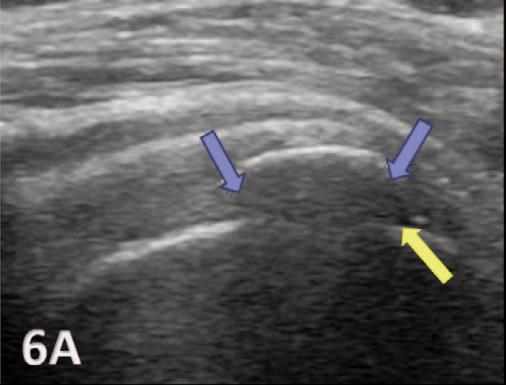

935 Utilizing Diagnostic Musculoskeletal Ultrasound for Assessment of the Infraspinatus Muscle and Tendon: Implications for Rehabilitation Professionals. Manske RC, Voight M, Wolfe C, Page P.